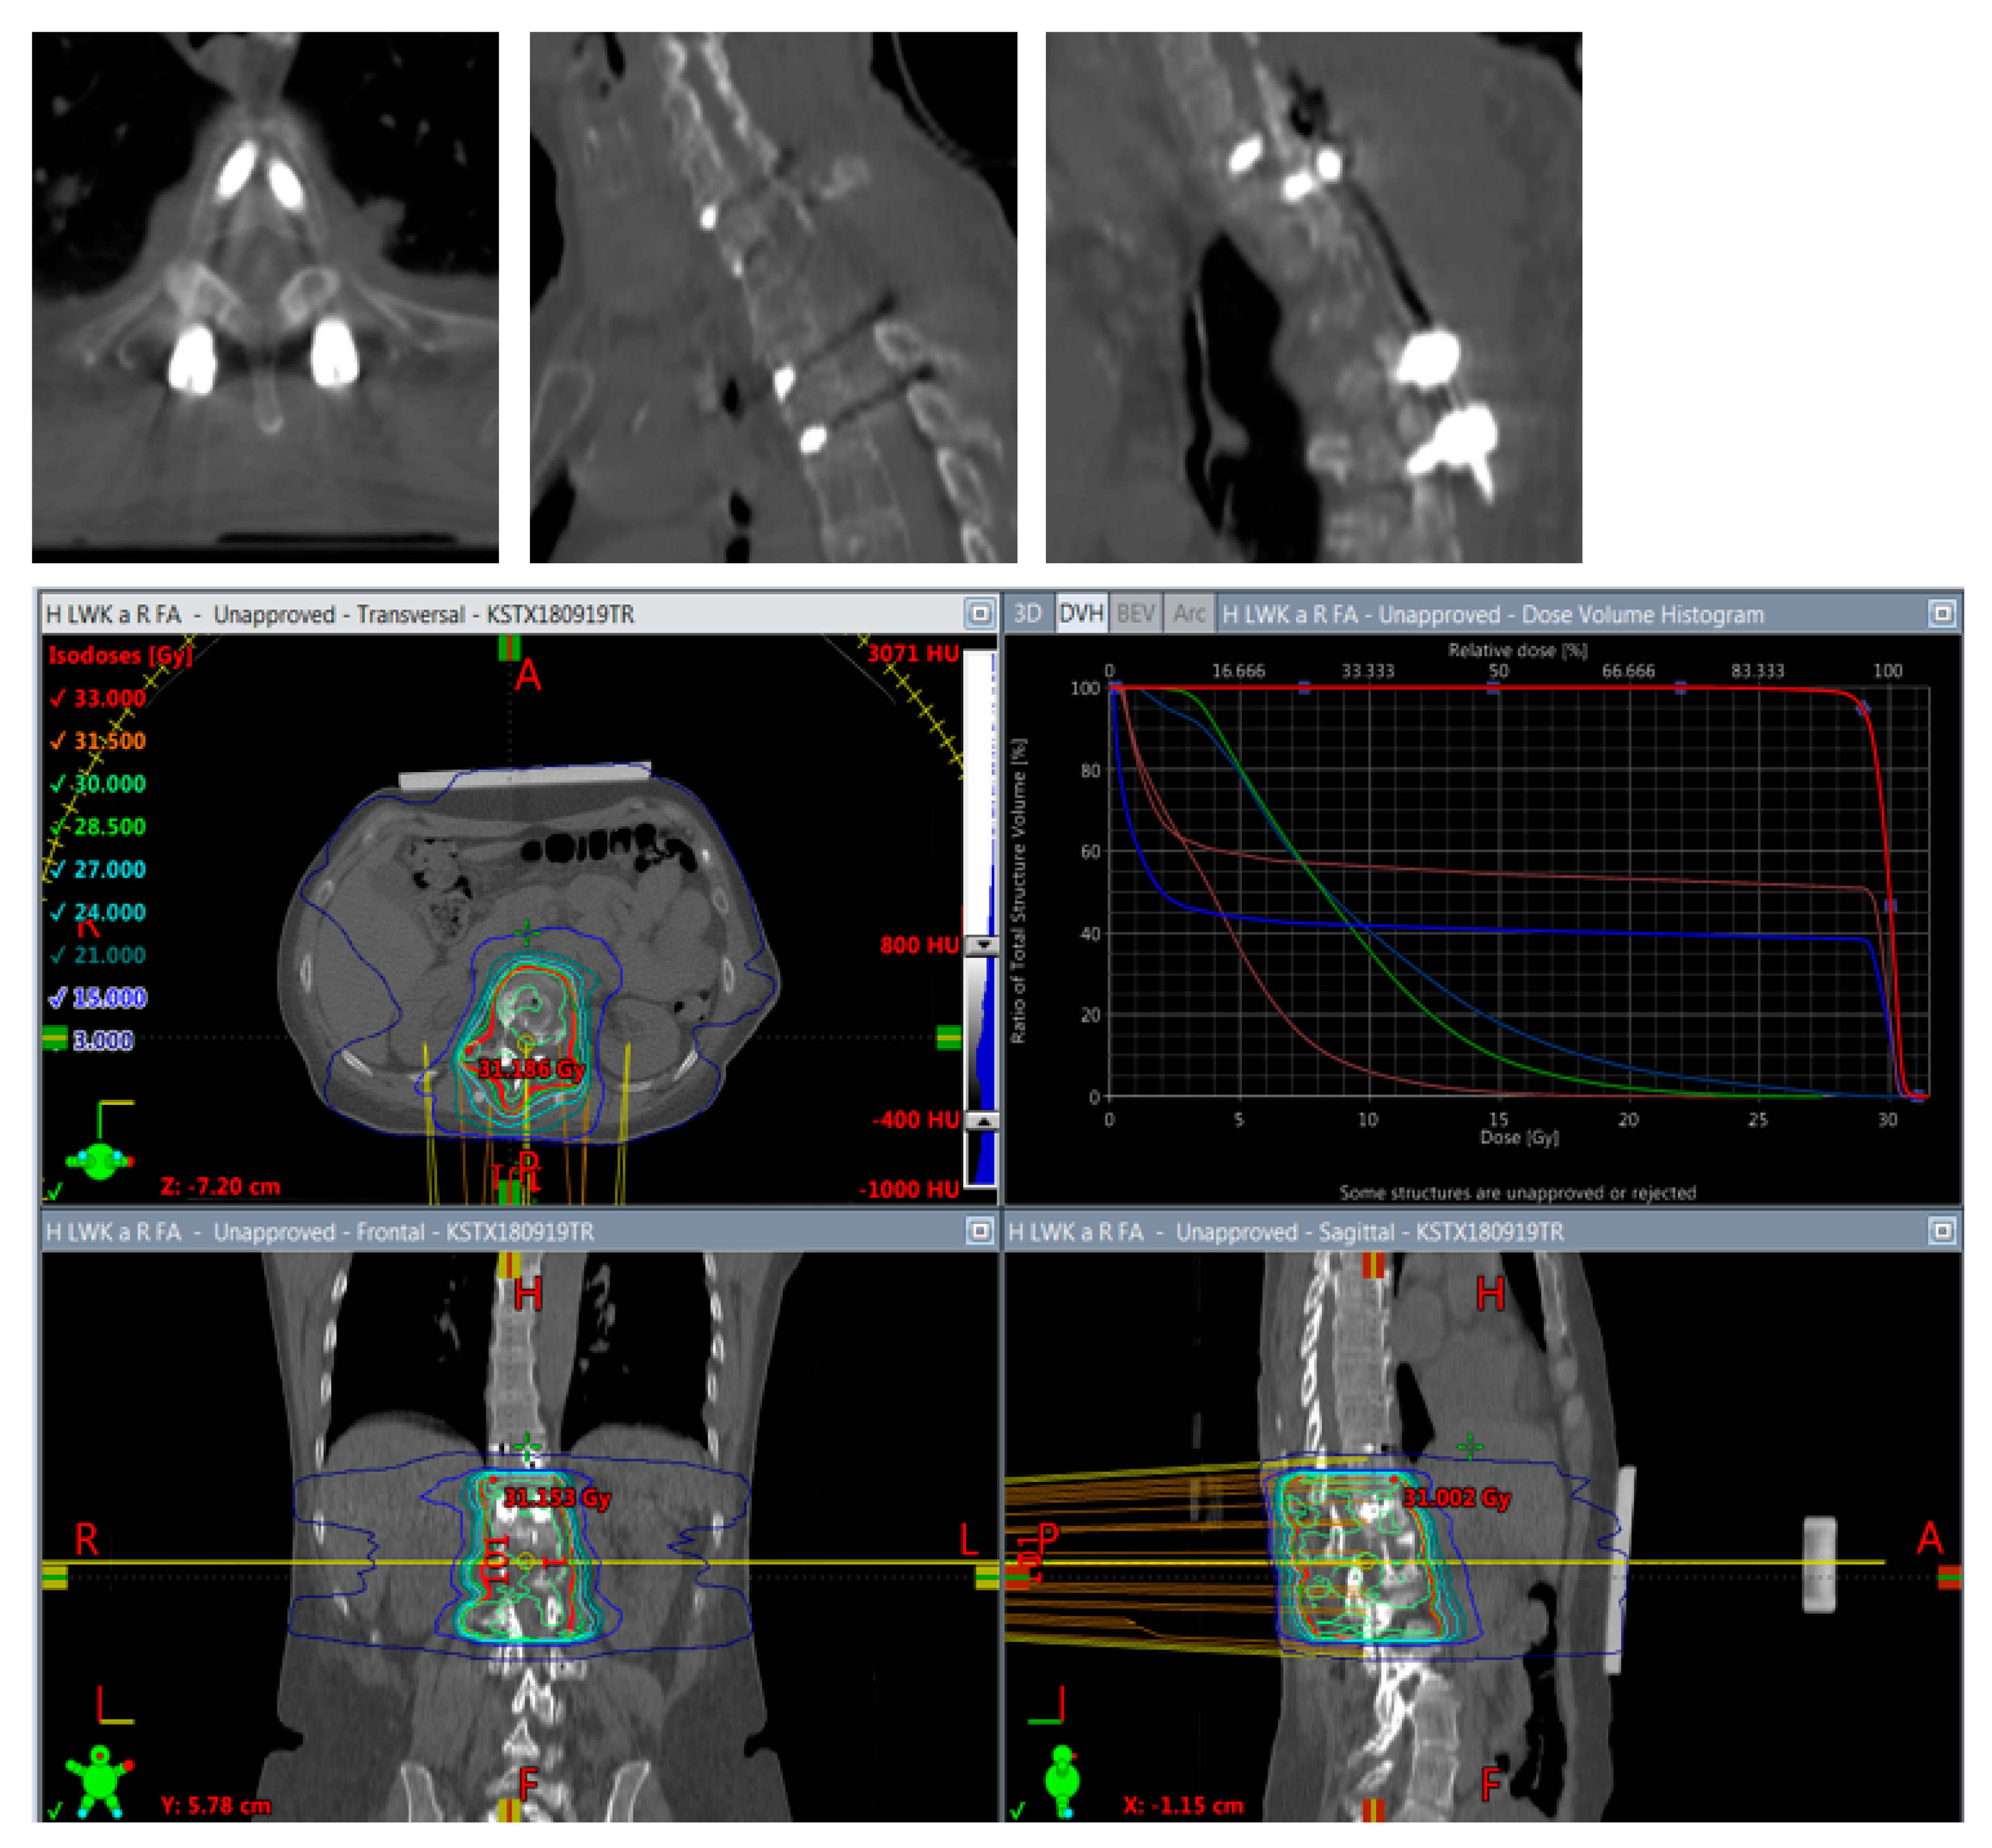

It has been shown in vitro [32] and in vivo [13] that CFR-PEEK reduces artifacts on CT and MR imaging and shows less perturbation effects on radiotherapy dose distributions [15] than titanium, fulfilling the requirements for an optimal application of radiotherapy (Figure 5 and Figure 6) and optimal long-term follow-up imaging. The advantages of CFR-PEEK on follow-up imaging have already been shown in the field of pyogenic spondylodiscitis [33].

Figure 5.

Planning of postoperative radiotherapy: titan. Planning of conventional radiotherapy (30 á 3 Gy) of the vertebral body plus all instrumented levels.

Figure 6.

Planning of postoperative radiotherapy: CFR-PEEK. Less artifacts allow smaller volume radiotherapy of 40/50 Gy á 2/2,5 Gy of the vertebral body alone. Dose escalation is possible and there is less risk to the spinal cord and others structures at risk.